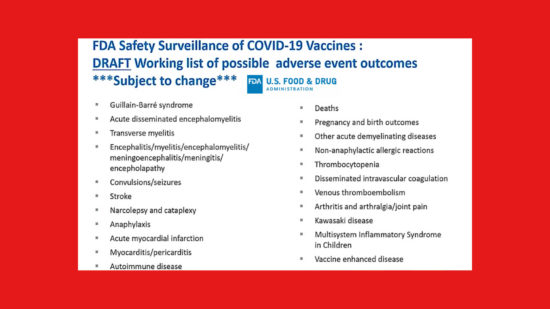

DEATH + 21 Serious Conditions as possible adverse effects of COVID-19 Vaccines

The Plan Is Unfolding for How Vaccines Will Be Monitored